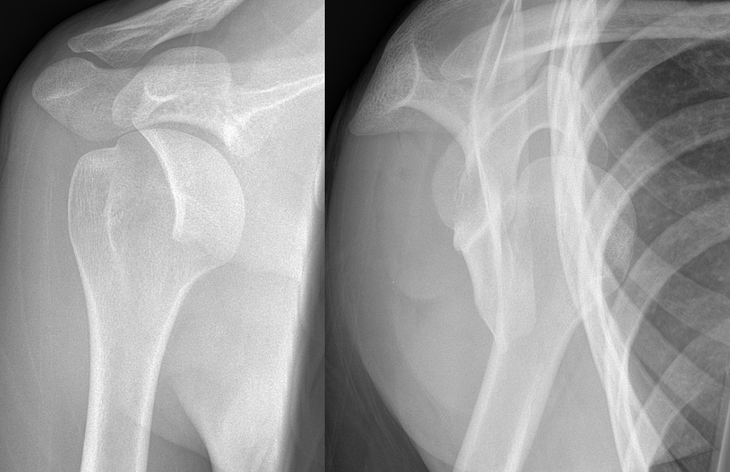

Briefly describe what is shown on the x-ray

Anterior shoulder dislocation, showing both AP and Y views.

How may an anterior dislocation present on plain radiographs?

Anterior dislocations can usually be spotted on the anterior-posterior film as the humeral head is visibly out of glenoid fossa, and the Y-scapular view also can confirm this. It is important to remember to check for concurrent bony injuries too.